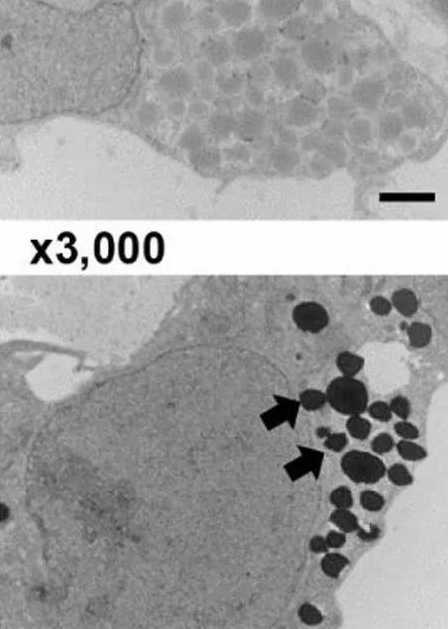

圖. 電鏡下細胞內(nèi)EPO的分泌囊泡